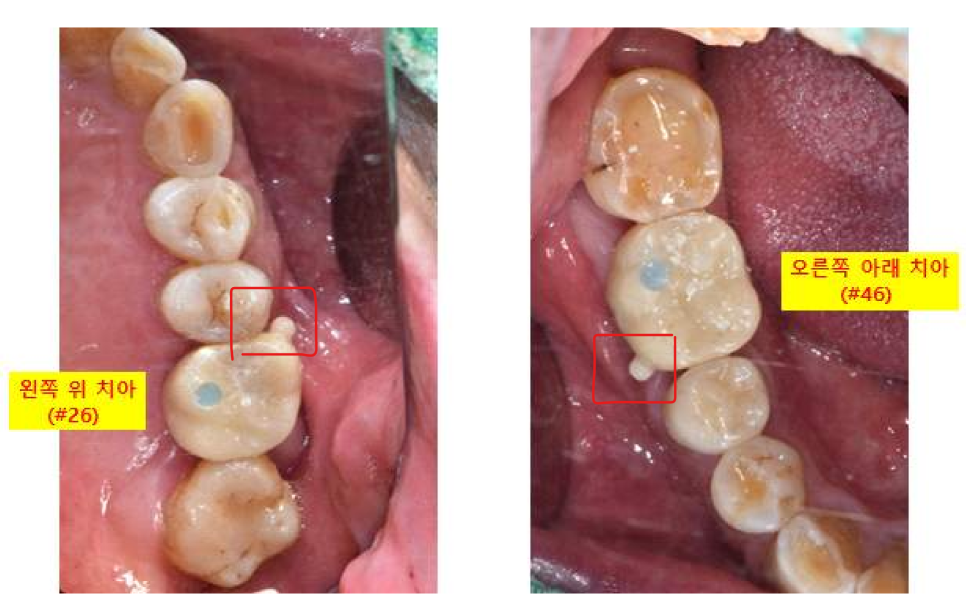

<치료 결정>

왼쪽 위 큰어금니 (26번치아) : 임플란트

오른쪽 아래 큰어금니 (46번치아) : 발치 + 임플란트 + 뼈이식

이 테스트 기간에 볼 쪽에 둥근 손잡이를 달아놓는데요,

완전히 붙일 때 보철을 잡고 뺄 수 있도록 만든 손잡이입니다.

완전히 붙일 때는 깔끔하게 제거해 드리니 걱정하지 마세요~^^

파란색으로 보이는 부분은 조이는 나사가

임플란트로 들어가는 통로입니다

통로에 있는 파란색재료는,

역시나 마무리할 때 치아색으로 다 메워 드립니다! 걱정하지 마세요!